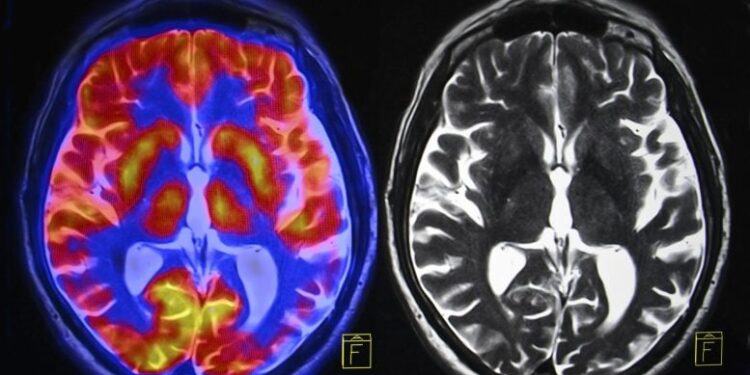

New analysis suggests menopause is related to mind quantity loss in key areas tied to reminiscence and feelings, together with larger charges of hysteria, melancholy, and sleep points. Hormone remedy didn’t forestall these modifications, although it might sluggish age-related declines in response pace. Menopause Linked to Mind Adjustments and Psychological Well being Challenges New analysis from […]